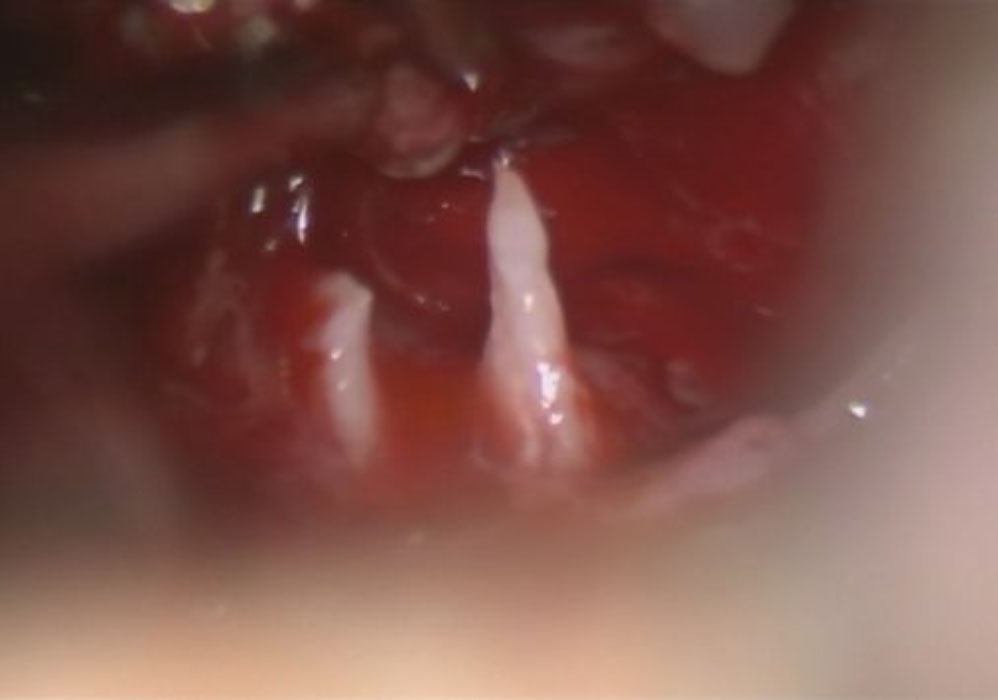

下垂体腺腫

頭蓋内腫瘍摘出術

No.’25_34  摘出 中

No.’25_34 摘出 後